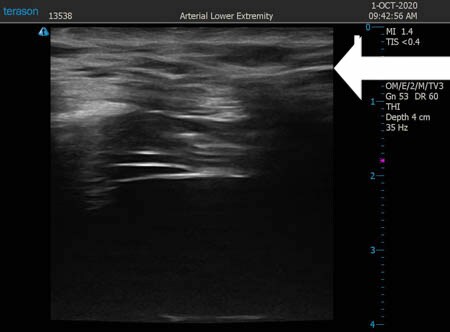

いつものように3Dタッチビュー(超音波)で

皮下脂肪層を評価してみましょう。

左肩甲骨横

↓ ↓ ↓